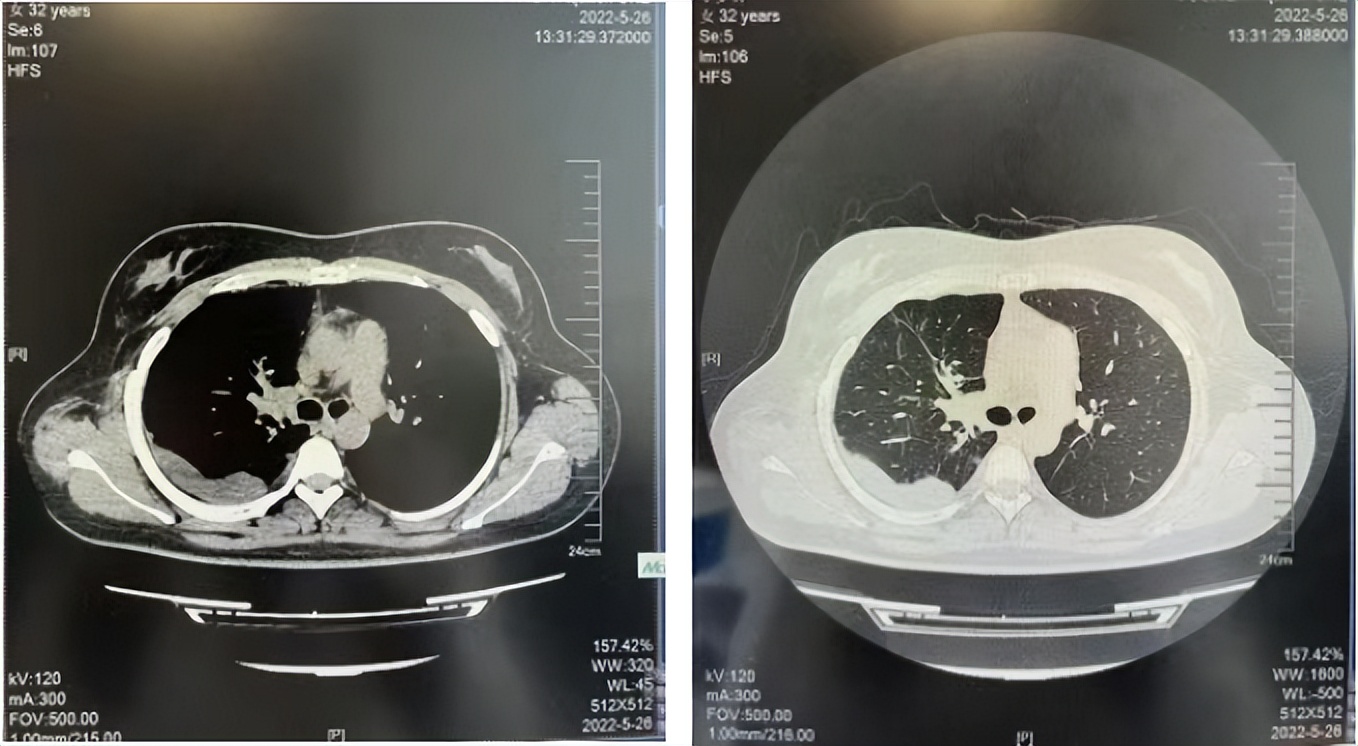

56岁,女性,无吸烟史饮酒史,既往体健。2023年02月患者体检发现肺占位性病变,胸部增强CT:右肺下叶后基底段结节;右侧锁骨上及纵隔内多发淋巴结肿大。PET-CT:右肺下叶周围型肺癌可能性大;1R、2L、3P、4R、4L及7组淋巴结转移可能性大。2023年02月就诊于本院胸外科行超声胃镜下纵隔肿物穿刺活检术,病理:结合免疫组化,符合肺腺癌。行NGS基因检测:EML4:exon20-ALK:exon20融合。PD-L1(克隆号22C3)TPS=55%。

2023年2月20日基线检查

2024年6月复查PR(最佳疗效)

2024年12月复查维持PR

2025年3月复查维持PR